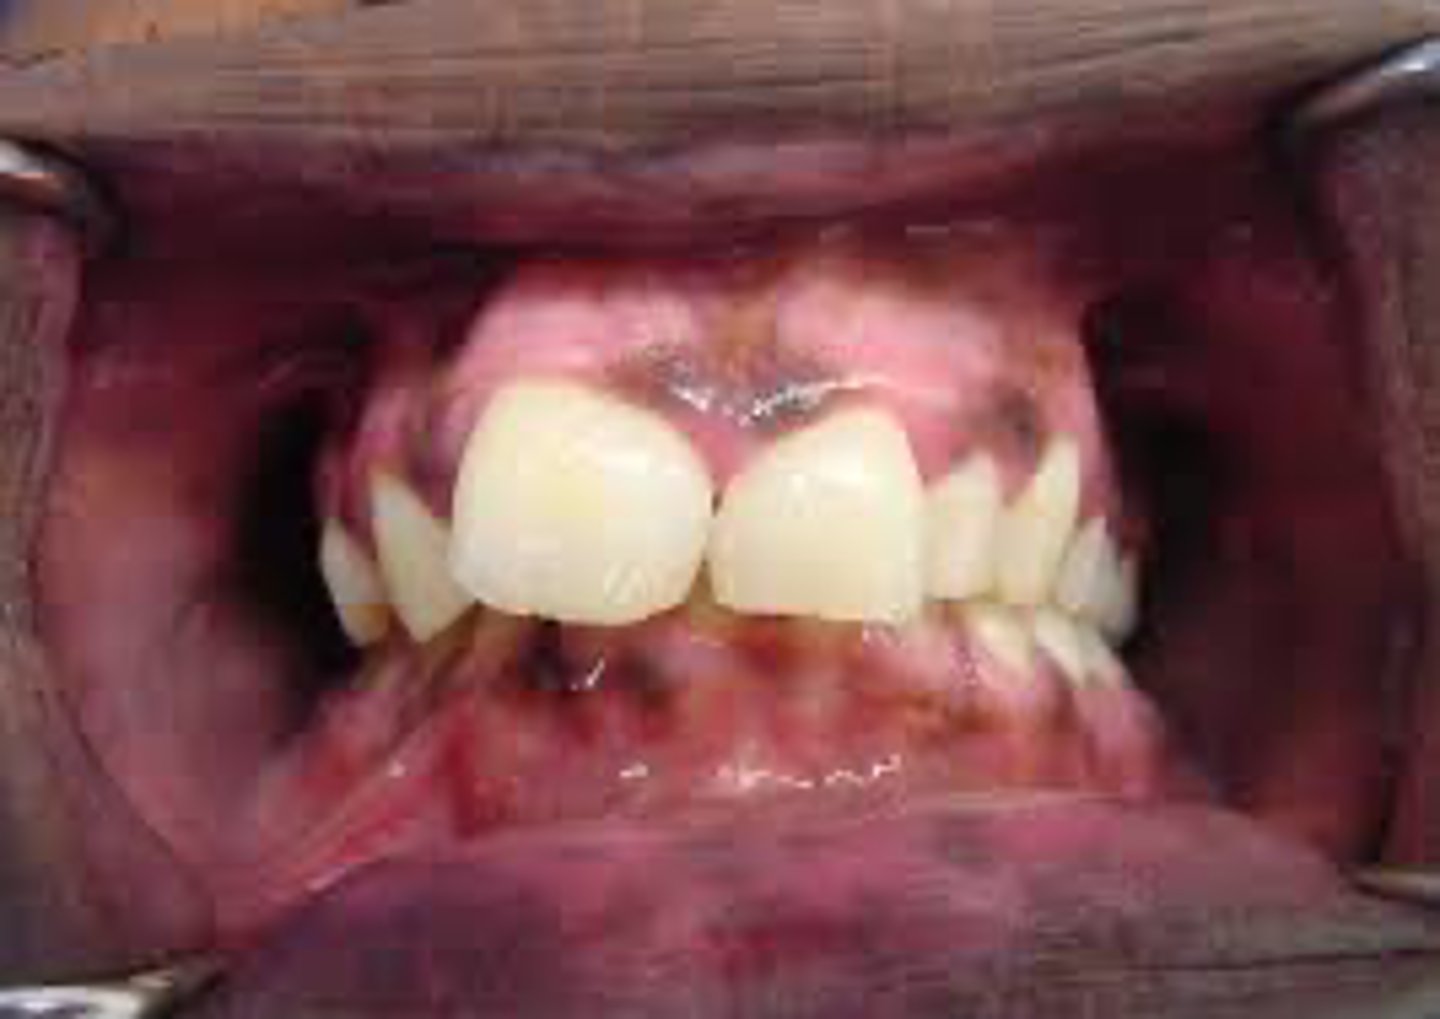

Which intraoral site is most commonly affected by Kaposi's sarcoma?

hard palate

A lesion appears purple on the palate and does not blanch or resolve over time. The patient has a history of HIV.

What is the most likely diagnosis?

Kaposi's sarcoma